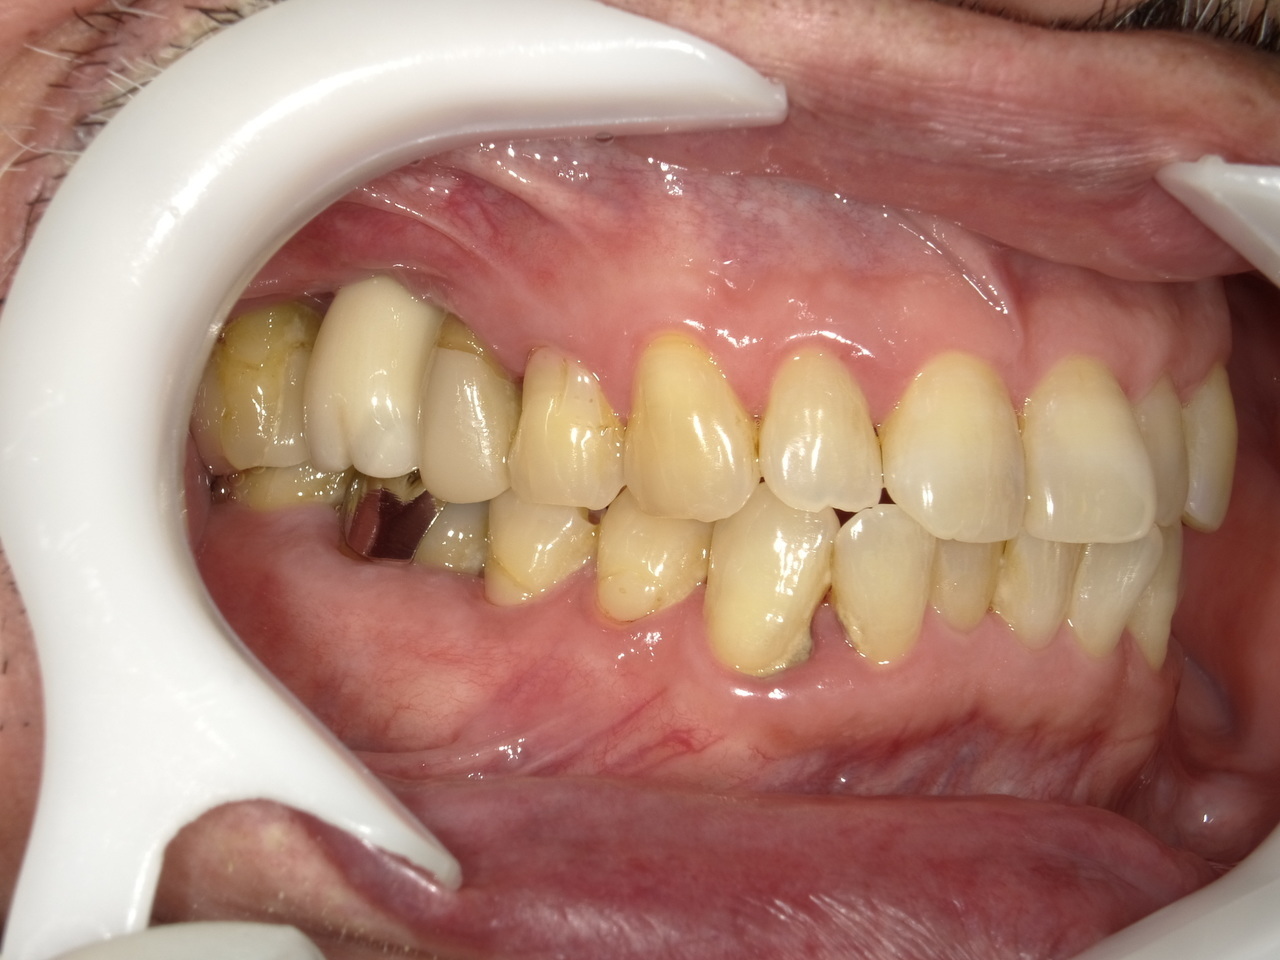

Before

枚方市のインプラントの症例

M・I 様 女性 70代

症状としては、左下56は、歯周病で欠損したと考えられるが、かなりの骨欠損をともなっていた。左上456に関しては、動揺が大きく、炎症が起き、排膿、および、歯性上顎洞炎を起こしていた。

治療法としては、動揺がひどくなってきて、炎症の症状もあったため、左上56の抜歯を希望。インプラント治療をその後、希望したため、左上4に関しては抜歯即時埋入。左上6に関しては、既存骨1から2mmでインプラント治療が厳しい状態であったが、グラフトレスサイナスリフトを行い、治療期間5か月はかかるということを説明して、インプラント埋入をおこないました。その後、2か月半後、大幅に骨が欠損している下顎56に対して、ショートインプラントを使用して、下顎神経の損傷を避けて、インプラント埋入を終えています。その後2か月後に光学印象で印象を行い、上顎刺億456歯、3ユニットのジルコニアブリッジを装着。下顎左側56に関しては、骨欠損が大きいため、歯冠長がだいぶ長くなるため、ジルコニアの連結冠を装着して治療を終えた。

治療結果は、上顎6に関しては、既存骨が少なく、厳しい治療ではありましたが、5か月で治療を終え、患者様の負担を最小限に抑えるができたと考えます。(従来のサイナスリフトでは、このようなケースでは1年以上、1年程度の治療期間がかかるか、治療が不可能と言われるケースだと考えます。)また、下顎は骨欠損が大きく、下歯槽管のリスクが起きることが考えられますが、ショートインプラントを使用することで安全に治療を行うことができました。

治療の期間・回数:治療期間5か月(上顎456 3ピースブリッジの治療は5か月(上顎既存骨が2mm程度しかなく、骨結合に時間がかかるケースであったために、5か月の治療期間が必要であった。)(左下56に関しては2か月半で治療を終えています。)治療回数は、13回。

治療の価格:1,474,000円(税込)

治療費の内訳:左上46および左下56のインプラント基本料(フィックスチャー及び手術費用、投薬費用、レントゲン費用、インプラント上部費用(アバットメントおよびジルコニアクラウンの費用用)330000円(税込み)×4本分 1320000円(税込)。左上5ジルコニアポンテック費用88000円(税込)。オプション費用、左上4抜歯即時埋入加算(人工骨費用を含む)+グラフトレスサイナスリフト費用 33000円(税込)、左上6グラフトレスサイナスリフト費用 33000円(税込)

治療のリスクや副作用:手術後に、痛みや腫れ、出血、合併症などを引き起こす可能性があります。噛む感覚がご自身の歯と異なる場合があります。見た目がご自身の歯と異なる場合があります。手術後にメインテナンスを継続しないと、インプラントが抜け落ちる可能性があります。